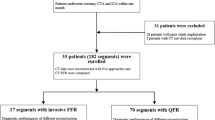

To evaluate the impact of an iterative reconstruction (IR) algorithm (advanced modeled iterative reconstruction, ADMIRE) on machine learning-based coronary computed tomography angiography–derived fractional flow reserve (CT-FFRML) measurements compared with filtered back projection (FBP). 170 plaque-containing vessels in 107 patients were included. CT-FFRML values were measured and compared among 5 imaging reconstruction algorithms (FBP and ADMIRE at strength levels of 1, 2, 3 and 5). The plaques were classified as, ‘calcified” or “noncalcified” and “≥ 50% stenosis” or “< 50% stenosis’, a total of four subgroups by consensus. There were no significant differences of CT-FFRML values among the FBP and ADMIRE 1, 2, 3 and 5 groups wherever comparisons were done at the level of subgroups (P = 0.676, 0.414, 0.849, 0.873, respectively) or overall (P = 0.072). There were 20, 21, 19, 19 and 29 vessels with lesion-specific ischemia (CT-FFRML ≤ 0.80) in FBP and ADMIRE 1, 2, 3 and 5 datasets, respectively, but no statistical differences were found (P = 0.437). Compared with CT-FFRML value of FBP dataset, the CT-FFRML values of 9 (5.3%) vessels from 8 patients (7.5%) in ADMIRE5 dataset switched from above 0.8 to below or equal to 0.8. There were no significant differences of the CT-FFRML values among the FBP and IR image algorithms at different strength levels. However, high iterative strength level (ADMIRE 5) was not recommended, which might have an impact on diagnosis of lesion-specific ischemia, although changes only occurred in a modest number of subjects.